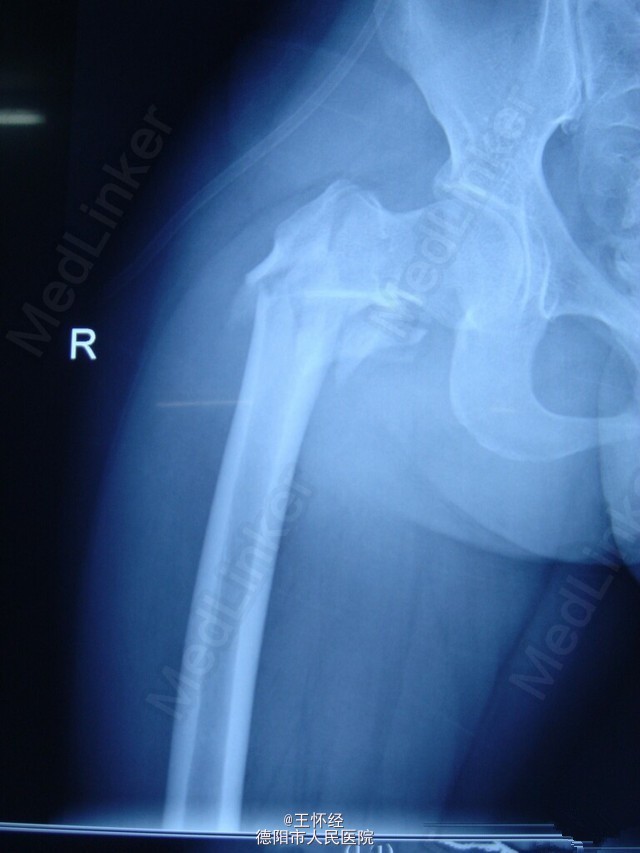

右侧股骨转子间骨折

患者女性,28岁,车祸伤急诊入院,右腿疼痛不能活动,x线检查发现转子间骨折。

右股骨转子间骨折

右侧转子间骨折